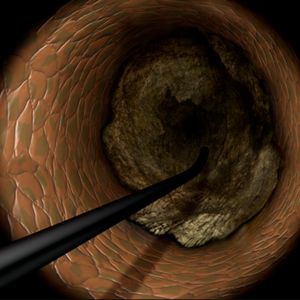

Join us for a live-streamed workshop where the world's top cardiologists gather to explore cutting-edge techniques in PCI (Percutaneous Coronary Intervention), with a special focus on the advanced Tip Detection Antegrade Dissection Re-entry (TD-ADR) method.

Innovative Techniques: Master the latest technologies, including the highly-regarded 3D wiring technique and TD-ADR, developed in Japan, and stay at the forefront of medical innovation.